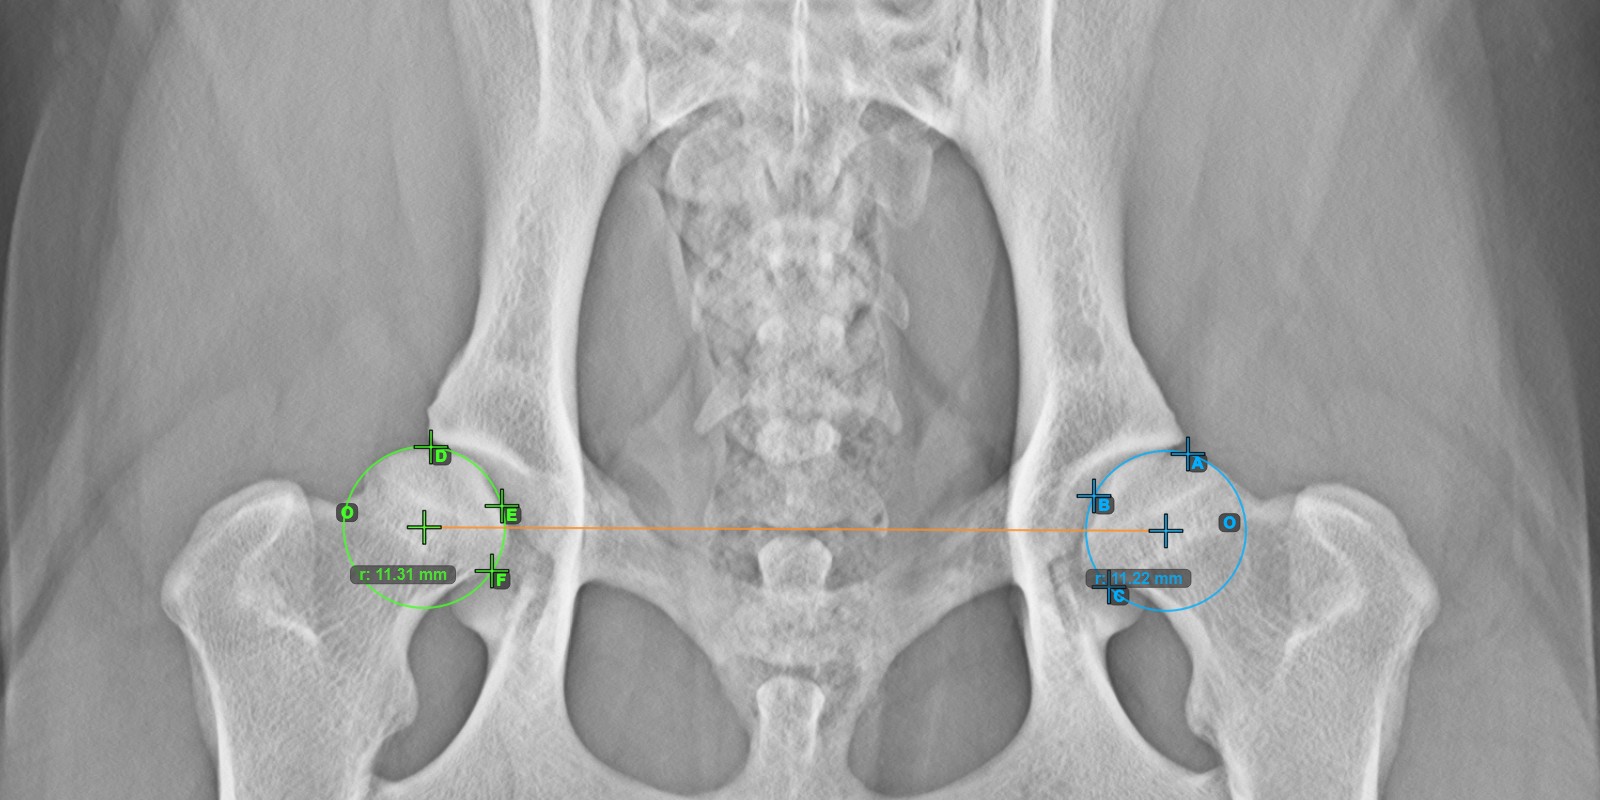

Start the measurement by marking the three points on the articular surface of the left Caput Femoris.

Mark the three points on the articular surface of the left Caput Femoris (outside of the Fovea Capitilis). Regardless of the order, make sure to mark the most cranial point, the most caudal point and the midpoint of the femoral head. A circle will be automatically constructed based on the three placed points.

The image below depicts the typical placement of the three points on the articular surface of the left Caput Femoris.